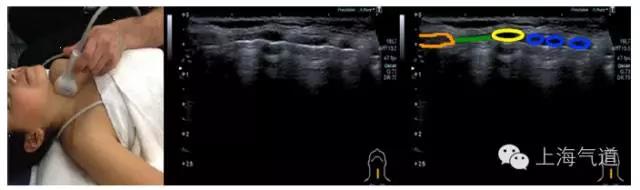

图7探头置于上胸部锁骨中线肋间隙处取纵切面,棕色为上下肋骨成像,并在后方形成了伪影(黄色),蓝色为胸膜(壁层和脏层)形成的高亮回声线,可伴随呼吸动作轻微移动(即胸膜滑动征)

图8探头置于肋下,右半横膈超声影像为高亮回声线(标记为橙色),吸气时会迎向探头方向移动。左半横膈因为心脏的位置而较难定位